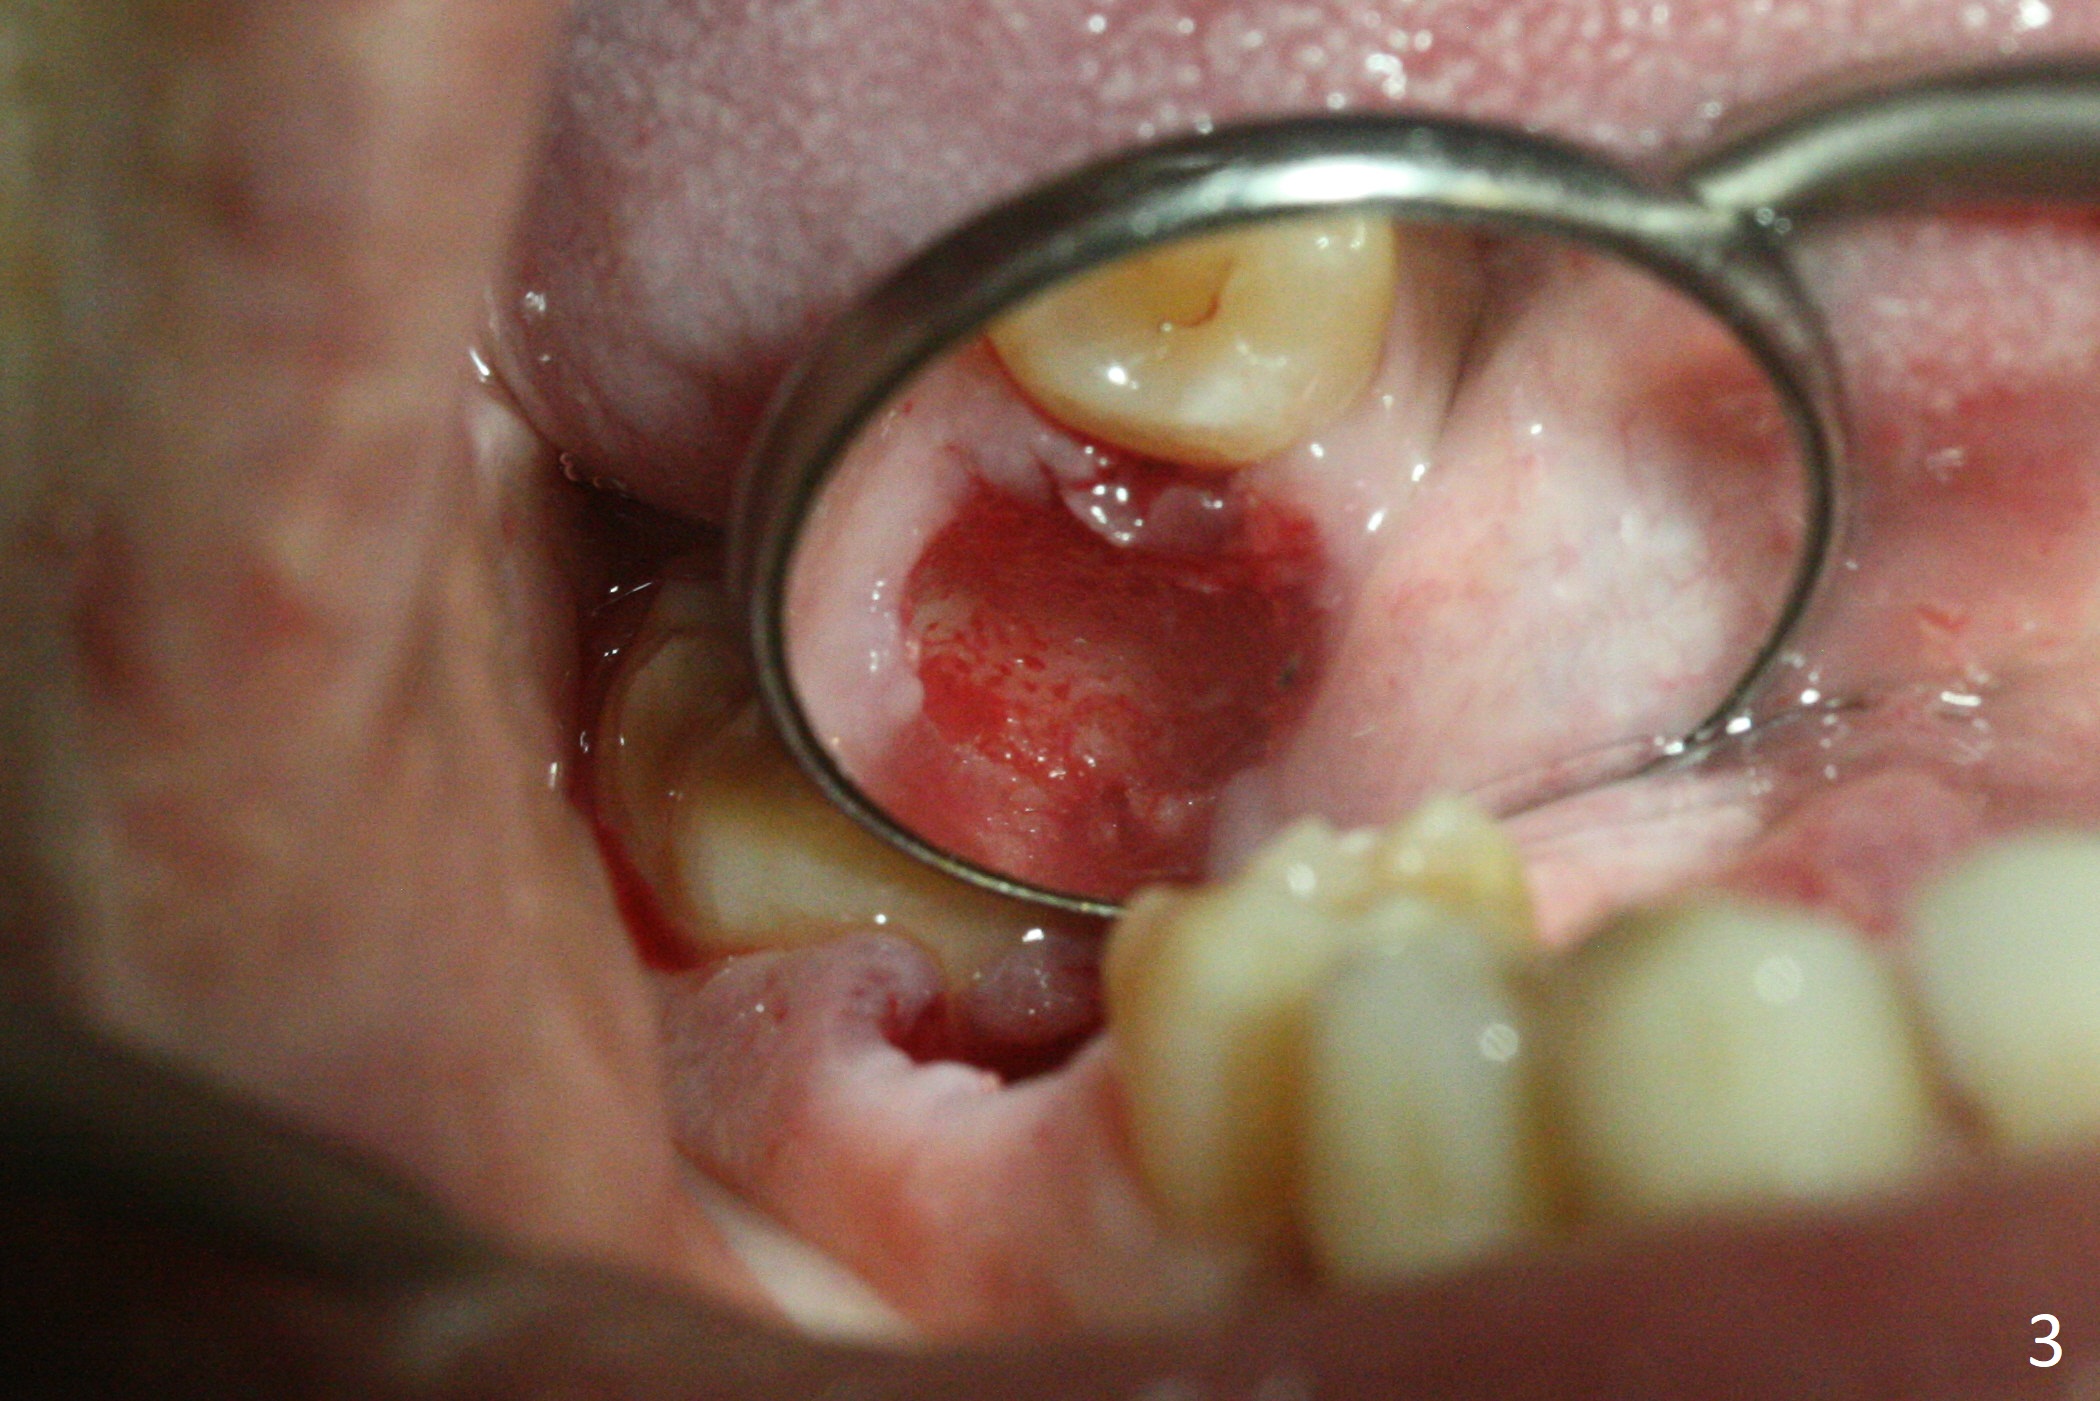

After removal of the residual roots at #30 (Fig.1), a thin septum (Fig.2 *) is removed with Rongeur (Fig.3). Following use of 4.8 mm Magic Drill, a 5x9 mm dummy implant is placed (Fig.4). To reduce socket gap (*), a 6 mm IBS implant is inserted with >50 Ncm (Fig.5). What is unexpected is heavy reduction in the height of a 6.5x4(3) mm abutment (A) because of the short crown height of the lower posterior teeth (Fig.1) and supraeruption of the tooth #3. The immediate provisional is unstable postop. The remade one dislodges soon, so does the abutment (Fig.6, 3 months postop). It appears that bone pattern in the distal socket changes.